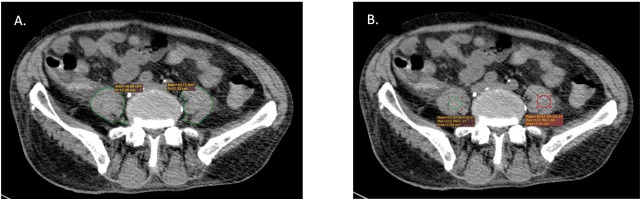

Objective: The main aim of this study was to assess the skeletal muscle in a COVID-19 cohort of critically ill patients by measuring the psoas area and density.

Material and methods: This is a retrospective study that included critically ill adult patients, COVID-19 positive, mechanically ventilated, with an ICU stay of over 24 hours, and who had 2 CT scans eligible for psoas muscle evaluation. In these patients, correlations between different severity scores and psoas CT scans were sought, along with correlations with the outcome of the patients.

Results: Twenty-two patients met the inclusion criteria. No statistically significant differences were noticed regarding the psoas analysis by two blinded radiologists. Significant correlations were found between LOS in the hospital and in ICU with psoas area and Hounsfield Units for the first CT scan performed. With reference to AUC-ROC and outcome, it is underlined that AUC-ROC is close to 0.5 values, for both the psoas area and HU, indicating that the model had no class separation capacity.

Conclusion: The study suggested that over a short period, the psoas muscle area, and the psoas HU decline, for both the left and the right sight, in adult COVID-19 patients in ICU conditions, yet not statistically significant. Although more than two-thirds of the patients had a negative outcome, it was not possible to demonstrate an association between the SARS-COV2 infection and psoas muscle impairment. These findings highlight the need for further larger investigations.